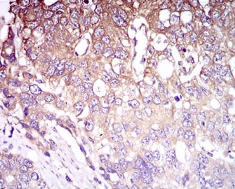

IHC    1/200 - 1/1000